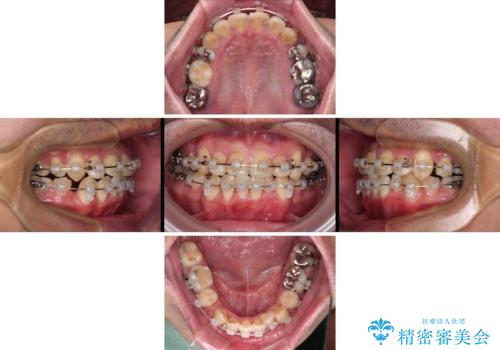

- 矯正装置

- クリアブラケット

- 治療期間

- 2年1ヶ月